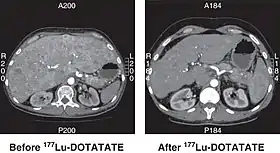

CT scan of non-functioning pancreatic NET before and 6 months after successful treatment with four cycles of 177Lu-DOTATATE. | |